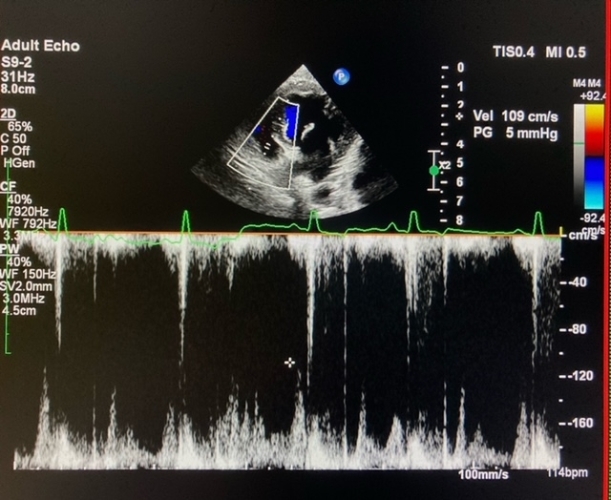

Echocardiology

Echocardiogram is basically ultrasound of the heart. On top of the basic heart check up in consult room, echocardiogram tells us more about the heart's structure, chamber size, pumping capacity, valves functions, blood flow etc. It has now become a routine diagnostic procedure for evaluating patients' heart problem severity and the need of specific heart medications.